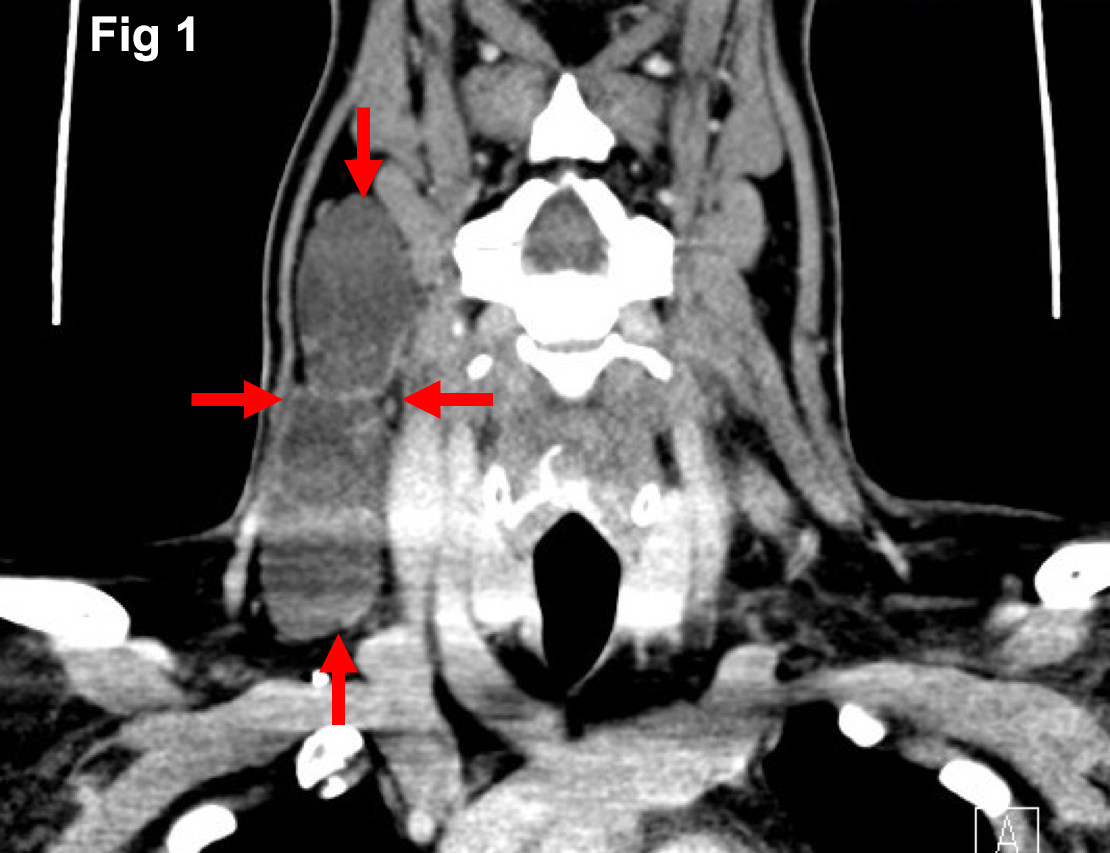

Initial computed tomography (Figure 1) demonstrated multiple right-sided thin walled cystic lesions within the upper to lower jugular chain and posterior triangle (levels II-V) forming a multi-loculated cystic lesion measuring approximately 10cm in maximal dimensions. Assessment with ultrasound (Figure 2a) revealed a multi-loculated cystic mass with thin walls and no intra-lesional flow, extending along the posterior margin of the right sternocleidomastoid muscle, posterolateral to the right internal jugular vein. The thyroid gland (Figure 2b) and major salivary glands appeared unremarkable. Ultrasound-guided fine needle aspiration cytology (FNAC) proved inconclusive.